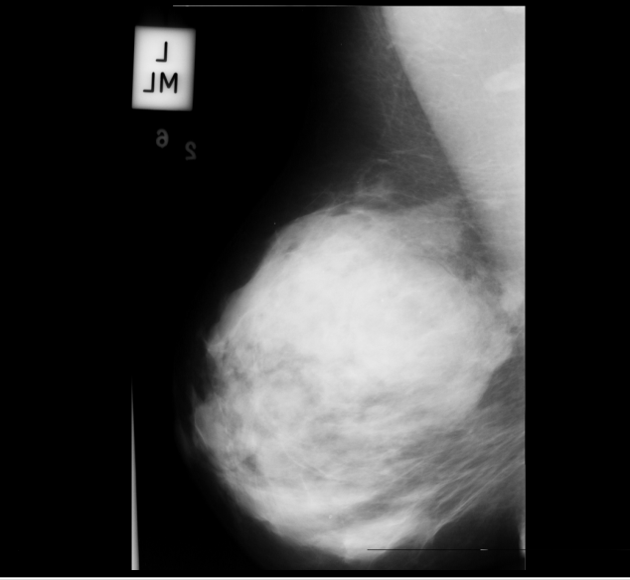

Neural networks require a large number of images as input for the training purposes. Because of limited resources of large dataset availability, the dataset used for this research is mini MIAS dataset [10]. It comprises of total 322 images which are further divided into a number of classes. Original size of each image in the dataset is 10241024. Sample images are shown in Figure 1.

Figure 5 shows a few sample images obtained after segmentation.